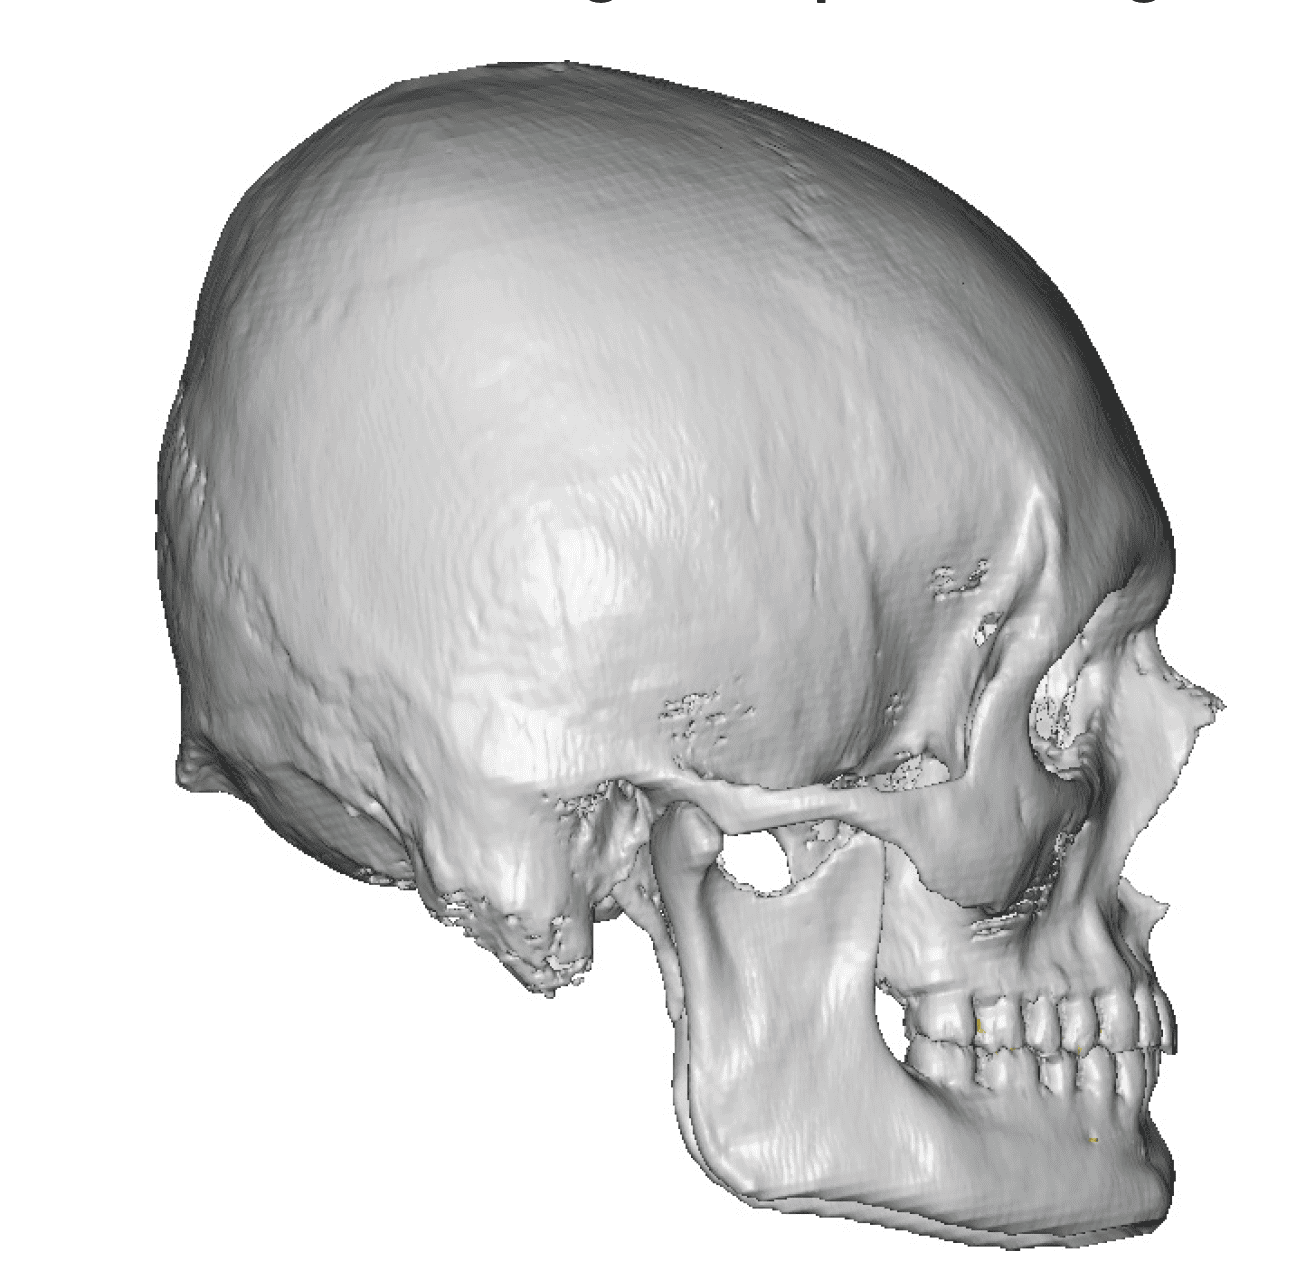

Patient 100

Desire for reshaping of an asymmetric flat back of the head in a shaved head male.

A combined back of the head reshaping procedure was done with a custom skull implant, sagittal ridge reduction and a right temporal muscle reduction.

Desire for reshaping of an asymmetric flat back of the head in a shaved head male.

A combined back of the head reshaping procedure was done with a custom skull implant, sagittal ridge reduction and a right temporal muscle reduction.